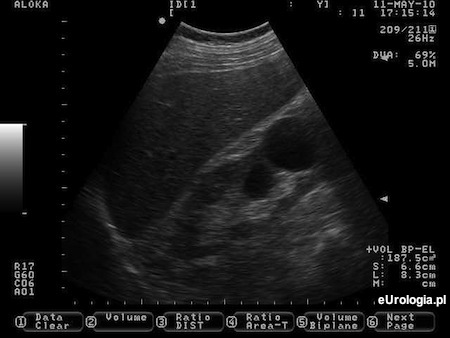

Fot. Torbiel prosta dolnego bieguna prawej nerki w USG.